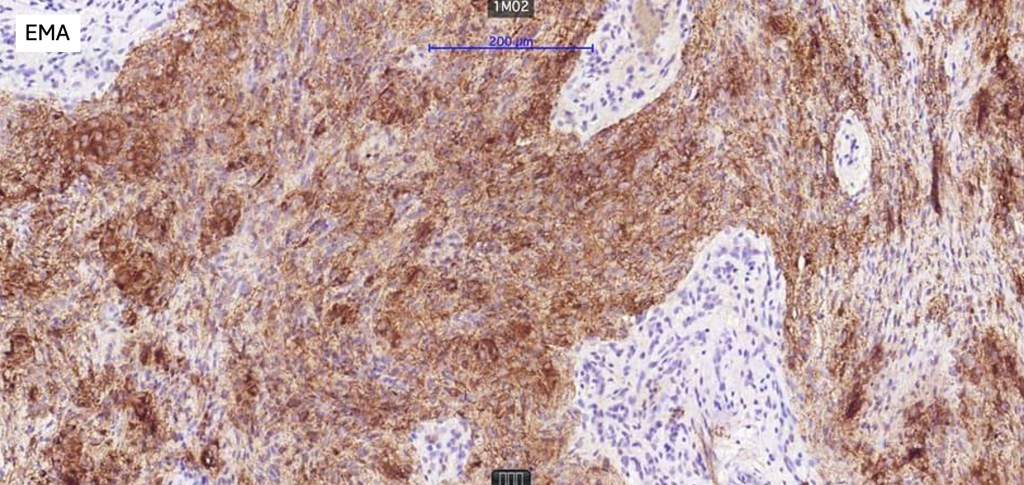

•AE1/AE3, GFAP, S100, SOX10, EMA,

•Variable p63, SMA & calponin +ve

.Syncytial myoepithelioma EMA & S100 +ve